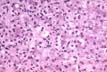

Mitoses

Fig 63 - Mitoses in normal liver are very rare.They increase in regeneration after injury.The periportal hepatocytes have the highest regenerative activity being better nourished and oxygenated than the rest of the lobule.This slide shows a periportal hepatocyte in mitosis following partial hepatectomy, in the rat which was iron loaded.